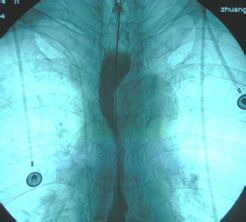

2、方法二:X线钡餐检查

如今,X线钡餐检查也是在临床上经常见到,该方法也是非常重要的手段之一,还可以为早期疾病研究提供可靠资料。如果结合细胞学和食管内镜检查的话,可以大大提高该疾病诊断的准确性。